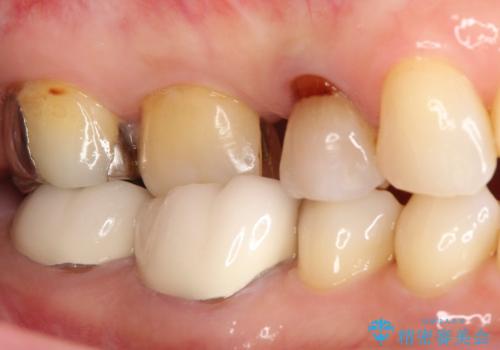

- 以前詰めた、インレーが外れたことを主訴に来院されました。

隣の歯にも虫歯を認めたためまとめて治療を行いました。

辺縁隆線にクラックラインを認め、破折防止のためにクラウンによる治療を希望されました。

歯間空隙は、患者様と相談した清掃性を考慮し、結果的に残すこととなりました。